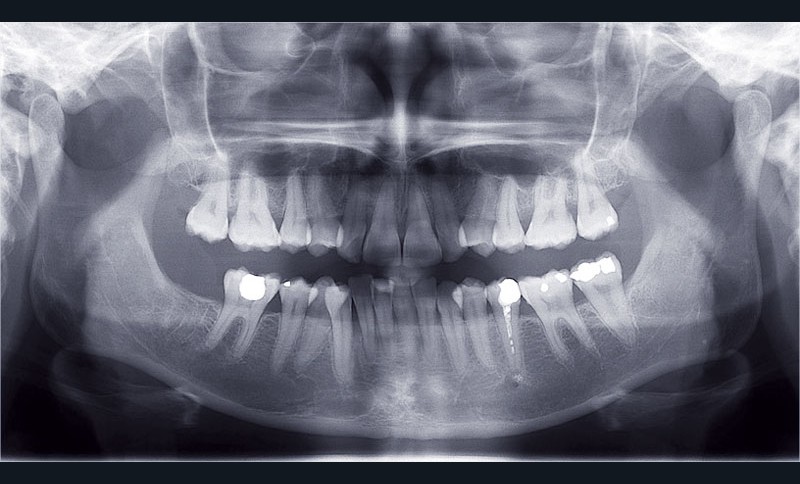

Cas n° 2

Nous lui avons donc proposé un traitement d’alignement avec maintien des 14 et 24 en position de 13 et 23 et optimisation du torque pour favoriser un développement des arcades et chercher à améliorer le sourire et le soutien labial.

Un appareillage Damon métal a été mis en place, réalisé à partir d’un set up numérique Insignia pour obtenir un contrôle précis des torques et de la forme d’arcade et réduire le temps de finition grâce à un collage indirect très précis.

De larges surélévations postérieures étalées ont été mises en place et la patiente a porté des élastiques précoces suivant les principes de la technique Damon. Les 14 et 24 rempliront le rôle des 13 et 23.

L’objectif, en utilisant la technique Insignia est de réduire le temps de traitement de 28 à 18 mois avec 12 rendez-vous (fig. 5 à 14).